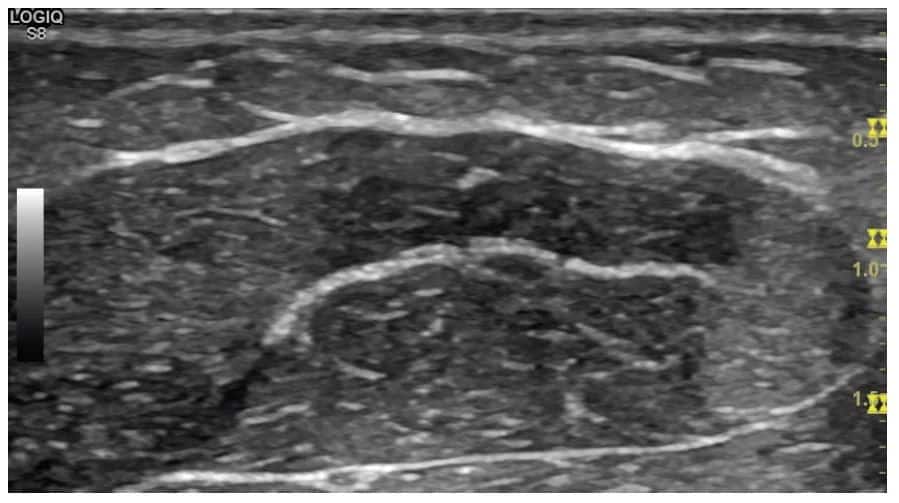

O entendimento da anatomia muscular é essencial para interpretar as imagens digitais, uma vez que o tecido muscular compõe a maior parte das imagens dos membros. Os músculos apresentam uma arquitetura distintiva, com fibras musculares hipoecóicas intercaladas por tecido conjuntivo hiperecóico, formando o perimísio. Quando vistos em corte transversal, os músculos podem exibir um padrão descrito como uma “noite estrelada”.

Os músculos são geralmente mais hipoecóicos (mais escuros) em relação a outros tecidos, como os tendões.

Utiliza-se a ultrassonografia para a avaliação de lesões musculares, incluindo distensões, rupturas parciais ou completas, e lesões relacionadas a traumas agudos ou crônicos.

A USG permite a visualização detalhada da arquitetura muscular, incluindo a identificação de áreas de hematoma, alterações fibróticas ou cicatriciais e a presença de calcificações. Além disso, a ultrassonografia permite monitorar o processo de cicatrização, orientando as decisões sobre o retorno do paciente às atividades físicas ou ao esporte.